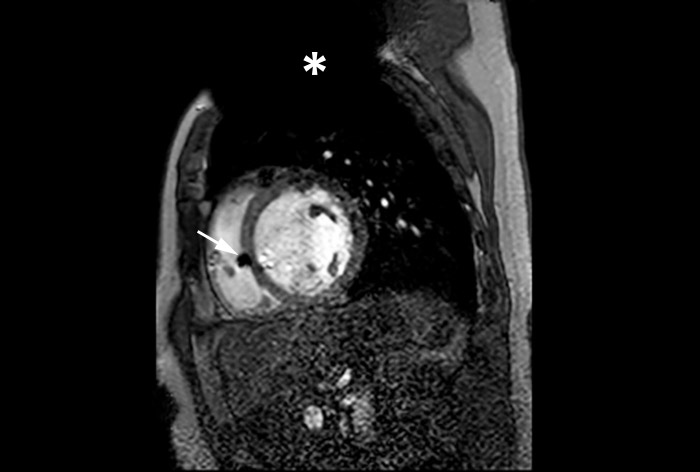

MRI of heart with MR Conditional ICD

A patient with an MR Conditional ICD and suspected myocarditis presented for MRI. This short axis view of the heart is created with an SSFP (steady state free precession) sequence on a Philips Achieva 1.5T system. The cardiac MRI exam reveals normal dimensions and regular function of the right and left ventricle. Note the ICD lead in the right ventricle (arrow) and the signal void in the left pectoral region, indicating the ICD-IPG (asterisk). Courtesy of Dr. Sommer.